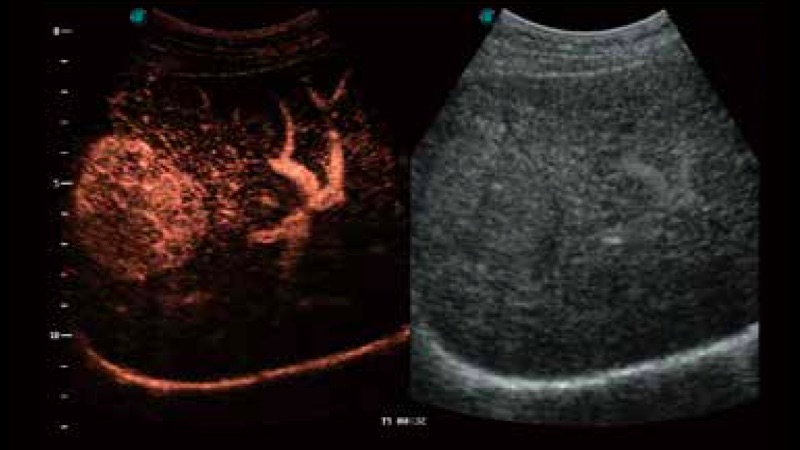

P12 Plus

彩色多普勒超声诊断系统

公海贵宾会员检测中心医疗通过不断的技术创新,为大众的生命健康提供持续关爱。P12 Plus采用全新一代超声成像平台,新平台旨在将真实还原组织解剖结构作为首要目标。平台采用全新集成化硬件模块,搭载新一代芯片,系统性能得到大幅提升,为您的诊断提供了丰富的临床信息。优异的图像表现,丰富的探头配置,全面的应用功能,为您日常诊断提供了可靠的助手。

凭借公海贵宾会员检测中心医疗先进的成像技术和优异的探头技术提供的清晰的图像表现,您可以更自信地做出临床决策。